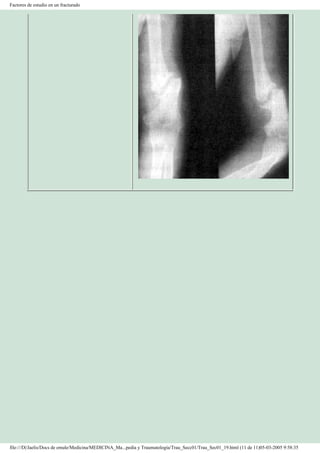

Este documento presenta el concepto de Ortopedia y Traumatología. Explica que esta especialidad médica se ocupa del estudio y tratamiento de las lesiones y enfermedades del aparato locomotor, incluyendo tanto las traumáticas como las congénitas o adquiridas. Relata brevemente los orígenes históricos de la ortopedia desde la antigua Grecia y su desarrollo a lo largo de los siglos hasta convertirse en una especialidad quirúrgica moderna gracias a los avances en cirugía, anest